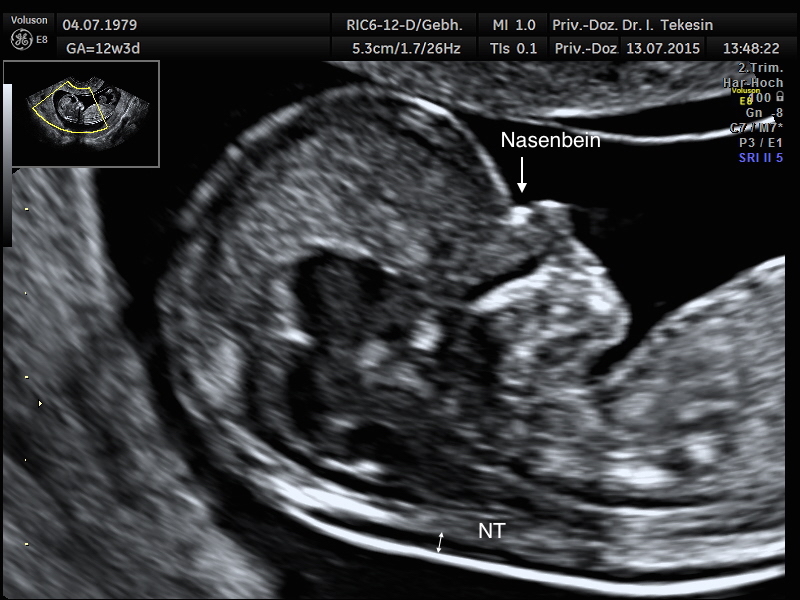

Normale Nackentransparenz (NT) und normaler Nasenbein (NB) in der 13. Woche

Darstellung der normalen NT und NB in der 13. SSW